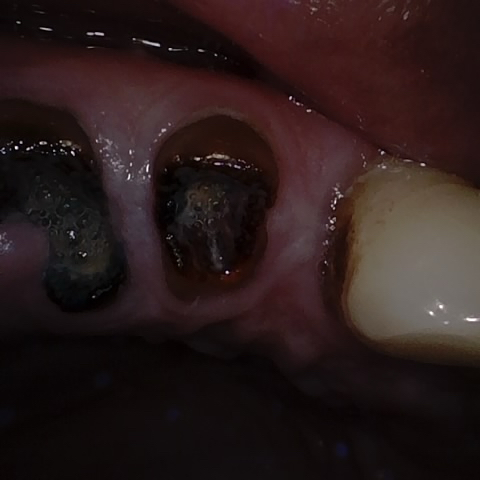

Annotated as "Good"